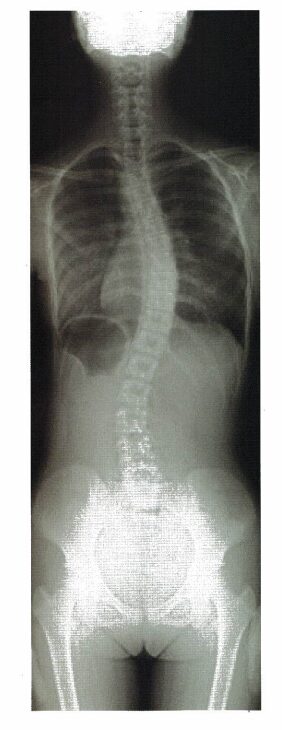

10 14歳の女子。運動器学校検診で側弯が指摘され、整形外科を受診。画像検査で胸椎カーブ35度の思春期特発性側弯症と診断された。画像を下に示す。医師より装具療法の適応が示された。

この症例に対する装具療法の選択で最も適切なのはどれか。

本症例のポイント

・14歳の女子(思春期特発性側弯症)。

・画像検査:胸椎カーブ35度。

・画像:側弯症の最大Th9

→ほかの選択肢が消去できる理由も上げられるようにしよう。

【側弯症の装具】

①TLSO装具:胸椎・腰椎の変形を制御する。①アンダーアームブレース、②ボストンブレースがある。

②CTLSO装具:頸椎・胸椎・腰椎の変形を制御する。ミルウォーキーブレースがある。

4.〇 正しい。ボストンブレースが、本症例(側弯症の最大Th9)に対する装具療法に該当する。

・ボストンブレースは、側弯症(Th7〜Th12)適応である。

5.× ミルウォーキーブレースは、側弯症(Th1〜Th6の場合)に対し適応である。

・Milwaukee装具(ミルウォーキー型装具)は、骨盤ガードルと頚部を支持するネックリングを金属支柱で連結して、側弯症に適応となり、脊柱の側弯の矯正のために胸椎パッドをつける。